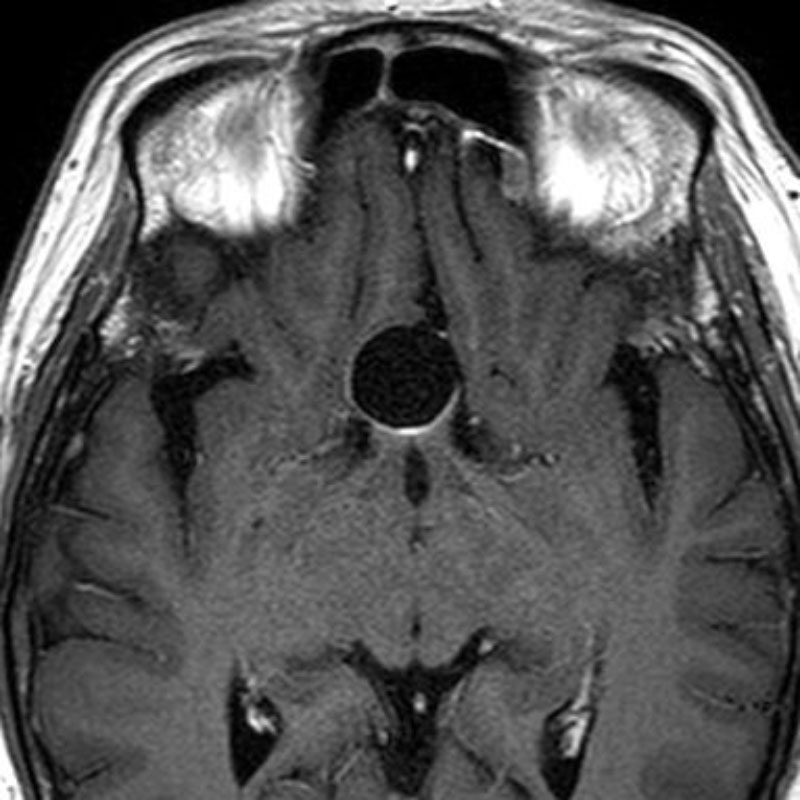

676

'25年10月

20代

脳幹部腫瘍

頭蓋内腫瘍摘出術

No.’25_78 手術前1

No.’25_78 手術前2